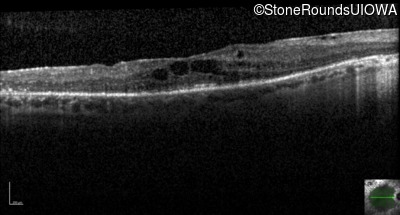

Optical Coherence Tomography - Right - 20/50 -1

Exemplar / OCT Stack